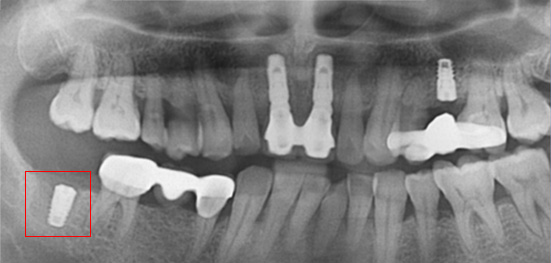

아래턱 어금니 발치 후 장시간 방치하여 잇몸 뼈 소실이 심한 상태로 내원. 뼈 이식 후 임프란트를 식립하였습니다.

잇몸 뼈 소실이 심한 상태로 내원

뼈 이식 후 치조골 밀도가 높아진 모습